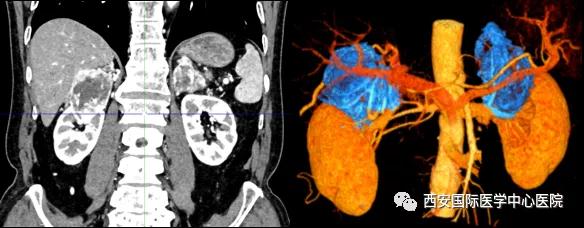

今年七十五歲的患者,來(lái)自陜西省商洛市,四月前因腰背部疼痛就診于當(dāng)?shù)蒯t(yī)院,行CT檢查發(fā)現(xiàn)“右腎、雙側(cè)腎上腺占位,前縱膈淋巴結(jié)腫大,雙肺多發(fā)結(jié)節(jié)、胸椎骨質(zhì)破壞,考慮轉(zhuǎn)移瘤”。為進(jìn)一步診斷治療,患者的兒子帶他來(lái)到西安某三甲醫(yī)院,查泌尿系CT提示“右腎占位性病變,多考慮腎癌,雙側(cè)腎上腺多發(fā)轉(zhuǎn)移灶,腹膜后多發(fā)腫大淋巴結(jié)”;行穿刺活檢提示“腎透明細(xì)胞癌”;并給予患者口服靶向藥物的治療方案。

自四月份至今,患者一直口服靶向藥物治療(阿昔替尼5mg 2次/日),期間無(wú)不良反應(yīng),目前腰背部疼痛癥狀也有所緩解,復(fù)查影像學(xué)資料提示瘤體較前縮小,腫瘤完整切除的可能性明顯提高;而且患者的兒子也是一名外科醫(yī)生,所以他更想為父親完成后續(xù)的手術(shù)治療。

患者一家慕名前來(lái)到西安國(guó)際醫(yī)學(xué)中心醫(yī)院找到楊增悅教授。楊增悅教授仔細(xì)看完患者的之前的影像學(xué)及病理資料后,診斷為:右腎透明細(xì)胞癌(T4N1M1);并安排他住院。而后,主管醫(yī)生及時(shí)為他完善了術(shù)前檢查及評(píng)估。7月15日,在麻醉手術(shù)中心柴偉主任、王彬榮副主任、李娟護(hù)士長(zhǎng)、李瑞剛護(hù)士長(zhǎng)及全體麻醉手術(shù)中心團(tuán)隊(duì)的有力保障下,成功完成了這臺(tái)“大”手術(shù)。

手術(shù)由楊增悅教授主持,舒濤主治醫(yī)師、王東主治醫(yī)師主刀,黃怡醫(yī)師、王平醫(yī)師協(xié)助完成。由于第四代達(dá)芬奇機(jī)器人更加靈活和精準(zhǔn)的特性,手術(shù)全程順利,尤其是完全精準(zhǔn)的“解鎖”了右腎動(dòng)脈和右腎靜脈的數(shù)十根交互纏繞的分支血管。術(shù)后患者麻醉恢復(fù)后生命體征平穩(wěn),順利返回泌尿外科普通病區(qū)進(jìn)一步康復(fù)。